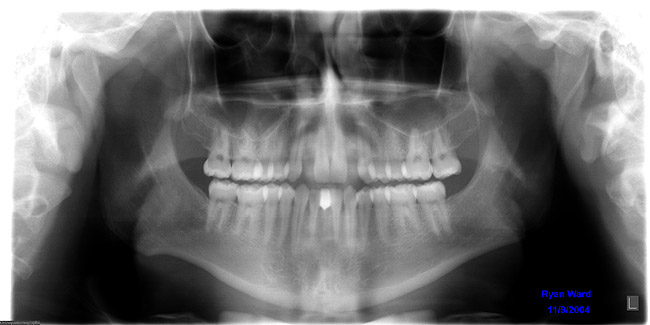

Figure 6 The orthodontic treatment created divergence of the coronal tooth structure and convergence of the roots around the edentulous spaces.

Figure 6

Figure 7 The panographic radiograph shows the roots of the cuspids encroaching upon the edentulous spaces. Additional orthodontic treatment will be required before implants can be placed to replace the missing teeth.

Figure 7